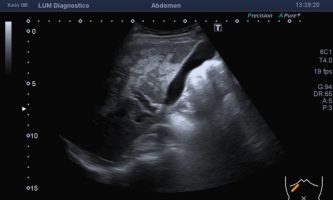

El médico de referencia le indica nueva ecografía de control, donde se observan múltiples y extensas lesiones focales hepáticas hiperecogénicas, redondeadas y confluentes, las cuales predominan en adyacencia a venas supra hepáticas, sin condicionar efecto de masa y sin alteración de la superficie hepática(fig. 1 y 2). Ante la valoración con Doppler color no presenta patrón de flujo peri ni intralesional y respeta el calibre de las venas supra hepáticas(fig. 3 y 4). Dada las características ecográficas se sospecha esteatosis focal multinodular confluente como principal diagnóstico presuntivo, siendo los diagnósticos diferenciales patologías de naturaleza infecciosa, tumoral o metastásica.